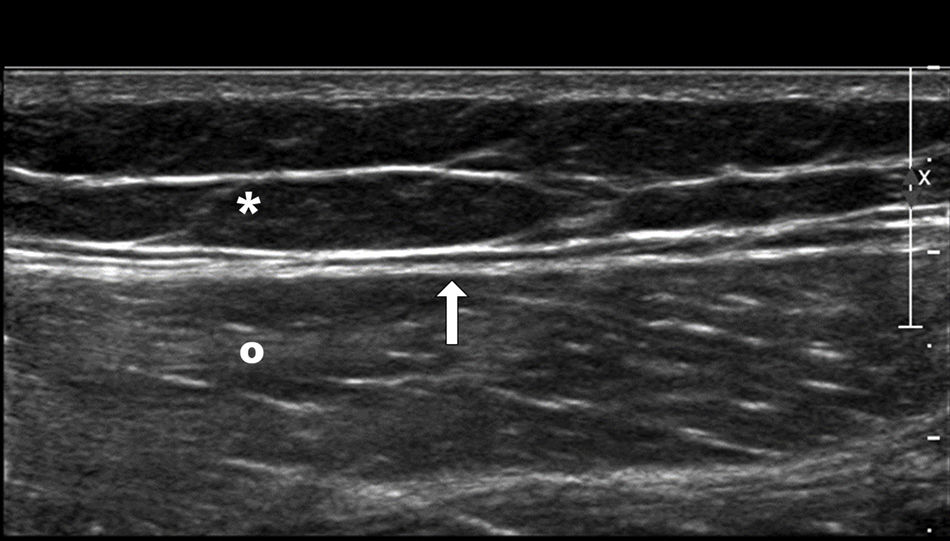

We aim to review the characteristics of Morel-Lavallée lesions and to evaluate their treatment.

Material and methodsWe retrospectively reviewed 17 patients (11 men and 6 women; mean age, 56.1 years, range 25–81 years) diagnosed with Morel-Lavallée lesions in two different departments. All patients underwent ultrasonography, 5 underwent computed tomography, and 9 underwent magnetic resonance imaging. Percutaneous treatment with fine-needle aspiration and/or drainage with a 6–8F catheter was performed in 13 patients. Two patients required percutaneous sclerosis with doxycycline.

ResultsAll patients responded adequately to percutaneous treatment, although it was necessary to repeat the procedure in 4 patients.

ConclusionsRadiologists need to be familiar with this lesion that can be treated percutaneously in the ultrasonography suite when it is not associated with other entities.